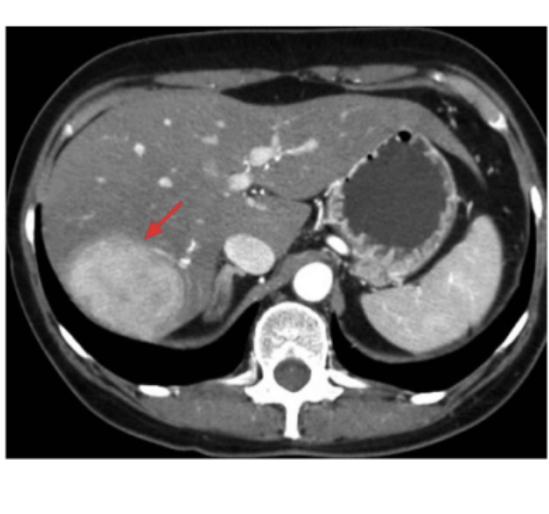

바로바로 간선종 또는 간샘종

간에 종양이 생기는건데

저 종양이 생각보다 큰게 보이지?

피검사로 진단할수는 없고

CT,MRI,혈관조영술로 확인 가능해